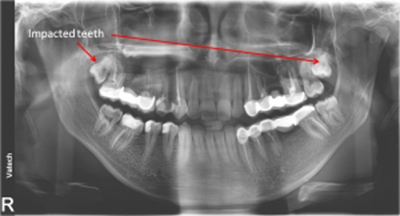

• Impacted teeth

impacted teeth